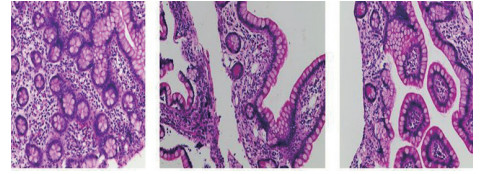

1 资料与方法患者男,30岁,因“腹胀、腹痛6 d,高热1 d”于2017年12月11日由广州南沙区中心医院转诊收入中山大学孙逸仙纪念医院全科医学科。患者本次起病前无明确病因或明显诱因。患者以左上腹轻微胀痛起病,进行性加重。南沙区医院查血常规:白细胞14.27×109/L,血小板50×109/L,中性粒细胞比例74.5%,嗜酸粒细胞1.02×109/L,嗜酸粒细胞比例7.2%。全腹CT+CTA提示:门静脉左右主干及其小分支栓子形成。后在3 d内连续复查血常规,提示血小板进行性下降,由50×109/L相继降至35×109/L、18×109/L;(嗜酸粒细胞计数及比例未能提供),并出现高热(体温39.5℃),因病情危重,遂转诊本院。入院时患者精神疲乏、高热,腹部胀痛难忍,伴有咳嗽。查体:体温38.6℃,心率87次/min,血压102/76 mmHg,指尖血氧饱和度90%~91%。双肺呼吸音粗,双肺均可闻及小水泡音。腹部稍膨隆,叩诊鼓音,左上腹及脐周轻压痛,无反跳痛。听诊肠鸣音减弱,约1~2次/min。当天查血常规示白细胞11.85×109/L,血小板23×109/L,中性粒细胞比例58.1%,嗜酸粒细胞3.5×109/L,嗜酸粒细胞比例29.5%。凝血常规提示:PT 15.9S,PTA 51.1%,PT/R 1.39,Fbg 1.59 g/L,PTINR 1.39,APTT 35.2 s,D-二聚体114.36 mg/L FEU(参考值范围0~0.55 mg/L FEU)。胸部+全腹部CT+CTA示“门静脉主干及左、右支、肠系膜上静脉近端栓子形成;腹主动脉及左侧髂总动脉小附壁血栓;左肺上叶尖后段、左肺上叶下舌段、右肺中叶及双肺下叶炎症;乙状结肠两段节段性管壁增厚,建议排外占位性病变;腹水、盆腔积液,大网膜炎性病变可能性大”。每日复查血常规,发现血小板进行性下降,最低至15×109/L(参考值范围125~350×109/L),嗜酸粒细胞计数及比例进行性升高,分别达到8.07×109/L(参考值范围0.020~0.52×109/L)和51.1%(参考值范围0.4-8.0%)。每日复查凝血常规亦提示凝血指标不断恶化,纤维蛋白原最低降至0.63 g/L。在予禁食、“美平(美罗培南)”抗感染、输注纤维蛋白原及血小板、维护水电解质平衡及营养支持的积极治疗的同时,还积极完善了以下检查寻找病因:①血液系统方面:血浆鱼精蛋白副凝实验:阳性(+);凝血功能实验:PT 15.5S↑,PTA 47.8%↓,PT/R 1.35↑,PTINR 1.36↑,APTT 40.4 s↑,AT-Ⅲ 57.7%↓,F-VII 32.8%↓,F-Ⅷ 68.1%↓,F-X 68.0%↓,F-XII 24.0%↓;纤维蛋白降解产物:381.4 mg/L↑;血栓弹力-血小板图:R时间10.3 min↑;角度18.5度↓;最大血块强度13.2 mm↓;MA(ADP)值5.6 mm↓。骨髓病理学:嗜酸性粒细胞增多(43%),巨核细胞减少(7个)。慢淋/淋巴瘤表型分析:获取和分析细胞数5.0万;粒细胞区百分比82.6%;淋巴细胞区百分比9.4%;单核细胞区百分比2.0%;CD45dim细胞区百分比1.3%;有核红及细胞碎片区域百分比4.6%。ETV6/PDGFRB融合基因、FIP1L1/PDGFRA融合基因(—)。骨髓细胞学病理结果:符合嗜酸细胞增多症;②消化系统检查:大便细菌培养鉴定及药敏提示无志贺、沙门菌生长,有真菌生长;大便难辨梭菌毒素检测(—);粪便找寄生虫、找阿米巴、寄生虫七项均为(—);消化肿瘤系列提示CA-125 244.8 U/mL↑;腹腔穿刺术穿出“血性腹水”,腹水CA-125 1006.0 U/mL↑,腹水找癌细胞(—);复查腹部CT+CTA:乙状结肠两段节段性管壁增厚,建议进一步检查;排外占位性病变;遂行PET-CT:提示全身未见明确恶性征象。行电子结肠镜示:内镜诊断:(1)回肠末段炎症;(2)乙状结肠炎症;(3)内痔。钳取组织送病理,提示:标本①(回肠末端)黏膜组织呈慢性炎,伴糜烂,一些嗜酸性粒细胞浸润(约35个/HPF);②(乙状结肠)黏膜组织呈慢性炎,伴糜烂,个别嗜酸性粒细胞浸润(约4个/HPF)。③风湿免疫系统方面:免疫八项、风湿四项:C反应蛋134.0 mg/L,余未见异常;总IgE 170 IU/mL↑;抗ENA抗体、狼疮两项、血管炎两项、免疫球蛋白G4、抗心磷脂抗体三项均为阴性;④其他感染病原学检查:乙肝、肝炎系列、性病三项、痰找抗酸杆菌、T-spot实验、流行性出血热、登革热抗体、登革热病毒NS1抗原、外斐氏试验、肥达氏试验、痰结核培养、骨髓培养、血液细菌、血液厌氧菌培养均为阴性。经过上述检查,初步考虑“特发性嗜酸性细胞增多症”,于12.15开始予“甲泼尼松龙40 mg静滴, 1次/d”及“低分子肝素0.6 ml皮下注射, 1次/d”抗炎抗凝治疗。患者病情及检验指标有所好转,热退、腹胀减轻,血常规提示血小板升至49 ×109/L,嗜酸粒细胞计数和比例均下降至正常,凝血常规提示D-二聚体降至47.90 mg/L FEU。但12-22患者自行进食多量米饭后突发腹胀痛较前加重,急查血常规提示白细胞升至21×109/L,血小板再次下降至15×109/L,D-二聚体升至97.28 mg/L FEU,全腹CTA提示“门静脉主干及左、右支、肠系膜上静脉近端新发栓子形成”,遂于当日转至ICU予“尿激酶20万U+肝素钠1250 U”溶栓治疗后予“低分子肝素0.6 ml皮下注射, 1次/12 h”序贯抗凝治疗。后患者病情渐渐稳定,至2018-1-18患者在“甲泼尼松龙12 mg口服, 1次/d”及“立伐沙班20 mg口服, 1次/d”的维持治疗下,血小板、嗜酸粒细胞计数及纤维蛋白原均回复正常,D-二聚体下降至3.52 mg/L FEU。但遗憾的是,此时患者再次进食大量米饭,约1 h后突发腹痛、气促,急行胸片+腹平片提示:“双侧膈下游离气体,考虑胃肠道穿孔可能;双下肺少许炎症,少量胸腔积液;腹部多量积气伴肠腔扩张”。遂即送手术室行全麻下“腹腔镜探查+坏死空肠切除+大网膜切除+肠系膜上动脉探查+空回肠双腔造口术”,术后病理提示标本①(大网膜)脂肪组织,部分坏死,合并慢性炎,伴一些中性粒细胞浸润,较多泡沫样组织增生,未见明确血栓,未见恶性改变。②(部分空肠)肠壁组织,部分肠壁全层坏死,合并慢性炎,肉芽组织增生,未见明确血栓,未见恶性改变。免疫组织化学:CD38浆细胞(+)、IgG(+)、IgG4(﹣)。术后继续予“立伐沙班10 mg/d”和“甲泼尼松龙8 mg/d”口服治疗,并于2018.2.4停用“甲泼尼松龙”。2.28复查全腹CTA,仍可见“脾静脉新发血栓,门静脉及肠系膜上静脉血栓较前好转”。3.20行空回肠双腔造瘘管泛影葡胺造影术提示“双腔造瘘管通畅,右中下腹小肠蠕动尚可,结肠各段及直肠通畅,未见对比剂外漏征象”。但患者合并了严重的短肠综合征,致严重低钾低钠血症和继发的代谢性脑病,病情再度转危。继续纠正电解质紊乱、补充营养,最终病情好转后于4.11行“造瘘口回纳修补术”。随访半年,患者仍口服“立伐沙班10 mg/d”抗凝治疗,复查血常规、凝血常规等各项指标均正常,但营养状况较差。

| 图 2 电子结肠镜病理(2017-12-19):示大量嗜伊红细胞,胞质丰富,核深染,细胞表面可见粉红色嗜酸颗粒 |